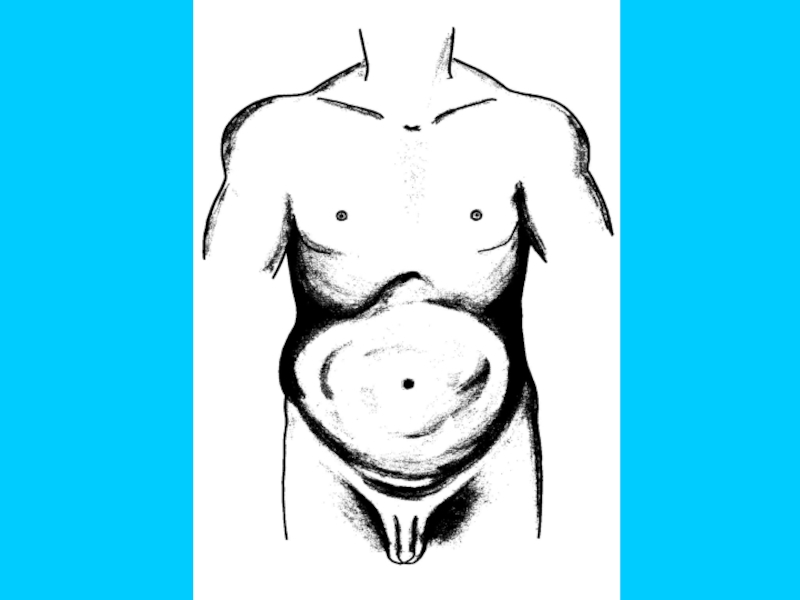

Вздутие живота

Нет общего вздутия

Общее

вздутие

Локальная асимметрия

Слайд 55

Асимметричное вздутие жи-вота при локализации причи-ны (опухоли?) на уровне дис-тальных

отделов толстой кишки. Симптом стоячей петли

Видимая кишечная пери-стальтика